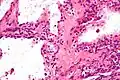

| Micrograph showing a pancreatic serous cystadenoma. H&E stain. | |